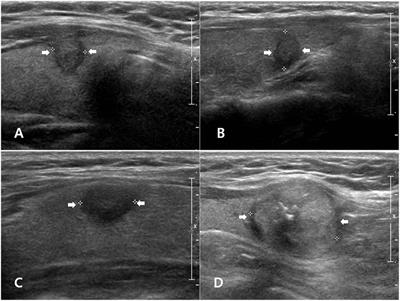

New cards

what thyroid pathology is shown here? note: these have a broad range of appearances and most often appear as solitary and homogeneous

thyroid adenoma

95